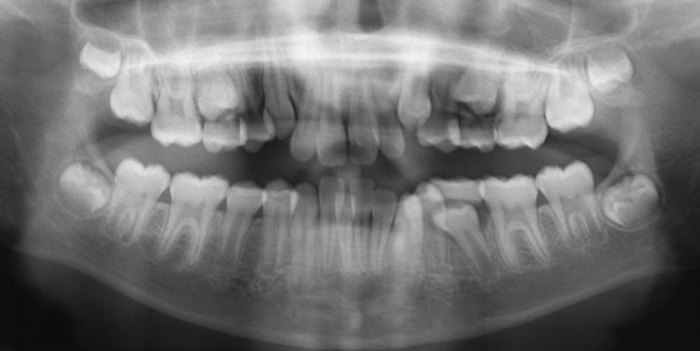

La paciente O.O. acude a nuestra consulta por:

– Canino 13 e incisivo lateral 42 en posición ectópica.

– Canino 23 incluido.

Con lo que decide realizarse un tratamiento de ortodoncia de duración de 24 meses con brackets damon Q.

CASO COMPLETO: